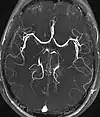

Magnetic resonance angiography (MRA) generates pictures of the arteries to evaluate them for stenosis (abnormal narrowing) or aneurysms (vessel wall dilatations, at risk of rupture). MRA is often used to evaluate the arteries of the neck and brain, the thoracic and abdominal aorta, the renal arteries, and the legs (called a "run-off"). A variety of techniques can be used to generate the pictures, such as administration of a paramagnetic contrast agent (gadolinium) or using a technique known as "flow-related enhancement" (e.g., 2D and 3D time-of-flight sequences), where most of the signal on an image is due to blood that recently moved into that plane (see also FLASH MRI).[47]

Techniques involving phase accumulation (known as phase contrast angiography) can also be used to generate flow velocity maps easily and accurately. Magnetic resonance venography (MRV) is a similar procedure that is used to image veins. In this method, the tissue is now excited inferiorly, while the signal is gathered in the plane immediately superior to the excitation plane—thus imaging the venous blood that recently moved from the excited plane.[48]